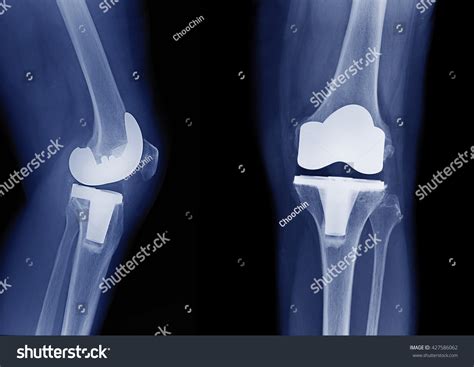

Total knee arthroplasty, or knee replacement, is a highly successful surgery designed to relieve pain and restore function in diseased or damaged knee joints. By looking at Knee Replacement Images, patients can see how an orthopedic surgeon removes the damaged cartilage and bone from the surface of the knee joint and replaces them with artificial components. These components are meticulously crafted to mimic the natural movement of a healthy knee.

The surgery generally involves three primary parts:

• The Femoral Component: A metal piece that attaches to the end of the thigh bone (femur).

• The Tibial Component: A metal tray that sits on top of the shin bone (tibia).

• The Patellar Button: A plastic piece that replaces the surface of the kneecap.